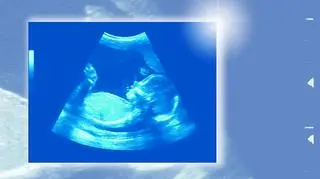

USG płodu w 20 tygodniu ciąży

20. tydzień ciąży – USG

20. tydzień ciąży to idealny czas na USG. Badania prenatalne w 20. tygodniu ciąży powinny rozwiać wszelkie obawy dotyczące zdrowia dziecka. W tym czasie wykonuje się m.in. USG połówkowe, dzięki któremu lekarz może określić, czy narządy wewnętrzne rozwijają się prawidłowo.

Uwaga! Jeżeli lekarz w czasie USG wykryje nieprawidłowości, zostaniesz skierowana do specjalistycznego ośrodka. Nie oznacza to, że dziecko jest chore, a jedynie, że konieczne są dalsze badania, w celu postawienia dokładnej diagnozy. Nie martw się na zapas!

Badanie USG w 20. tygodniu pomaga w określeniu ilości wód płodowych, ułożenia dziecka oraz funkcji łożyska. To również podczas tego badania rodzice mogą uzyskać niemal pewną informację o płci dziecka - oczywiście, jeżeli ułożenie malucha w brzuchu będzie odpowiednie. Niektórzy rodzice mają to szczęście, że wiedzą już wcześniej jaka jest płeć dziecka, inni nie mają takiej informacji do samego porodu.

Jak wygląda dziecko w 20. tygodniu ciąży ? Nie różni się już niemal niczym od noworodka. Możesz się o tym przekonać, kiedy dostaniesz zdjęcia płodu po wykonanym USG , zwłaszcza USG 4D, które dostępne jest już w wielu gabinetach ginekologicznych. Jedną z najpoważniejszych zmian, do której dochodzi w tym okresie jest utwardzanie się kości. Do tej pory szkielet dziecka tworzyły delikatne chrząstki – teraz zaczynają kostnieć. Zmienia się też skóra dziecka – jest pokryta owłosieniem oraz mazią (zarówno jedno jak i drugie znikają przed porodem) i staje się znacznie grubsza.